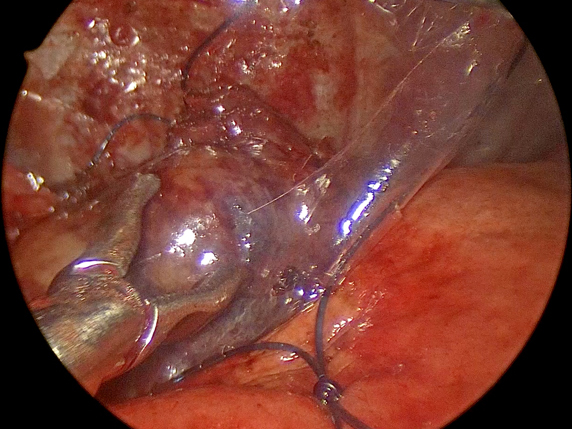

手術中の様子

胸腔鏡下での腫瘤病変の確認

摘出した後に特殊な回収袋で回収

摘出した腫瘤病変(病理検査結果:胸腺腫)